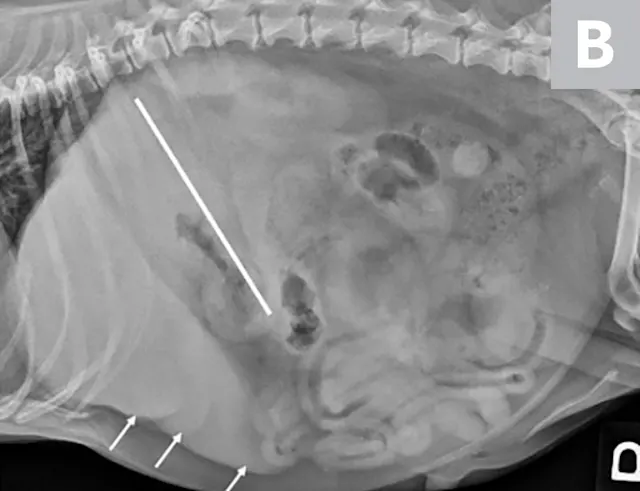

Right lateral radiographs of a clinically normal dog (A) and an 11-year-old neutered male dachshund with diabetes mellitus (B). The dog with diabetes mellitus has a pendulous abdomen and an enlarged liver (ie, hepatomegaly) with rounded margins that extend caudal to the costal arch (B; arrows). The gastric axis (solid lines; aligned with the gastric fundus dorsally to the antrum ventrally) is parallel to the ribs in the clinically normal dog but caudally displaced in the dog with hepatomegaly. Common differential diagnoses for generalized hepatomegaly are vacuolar hepatopathy due to endocrinopathies or other metabolic disease (eg, lipidosis), infectious and noninfectious inflammatory disease, neoplasia, storage disease, and venous congestion.